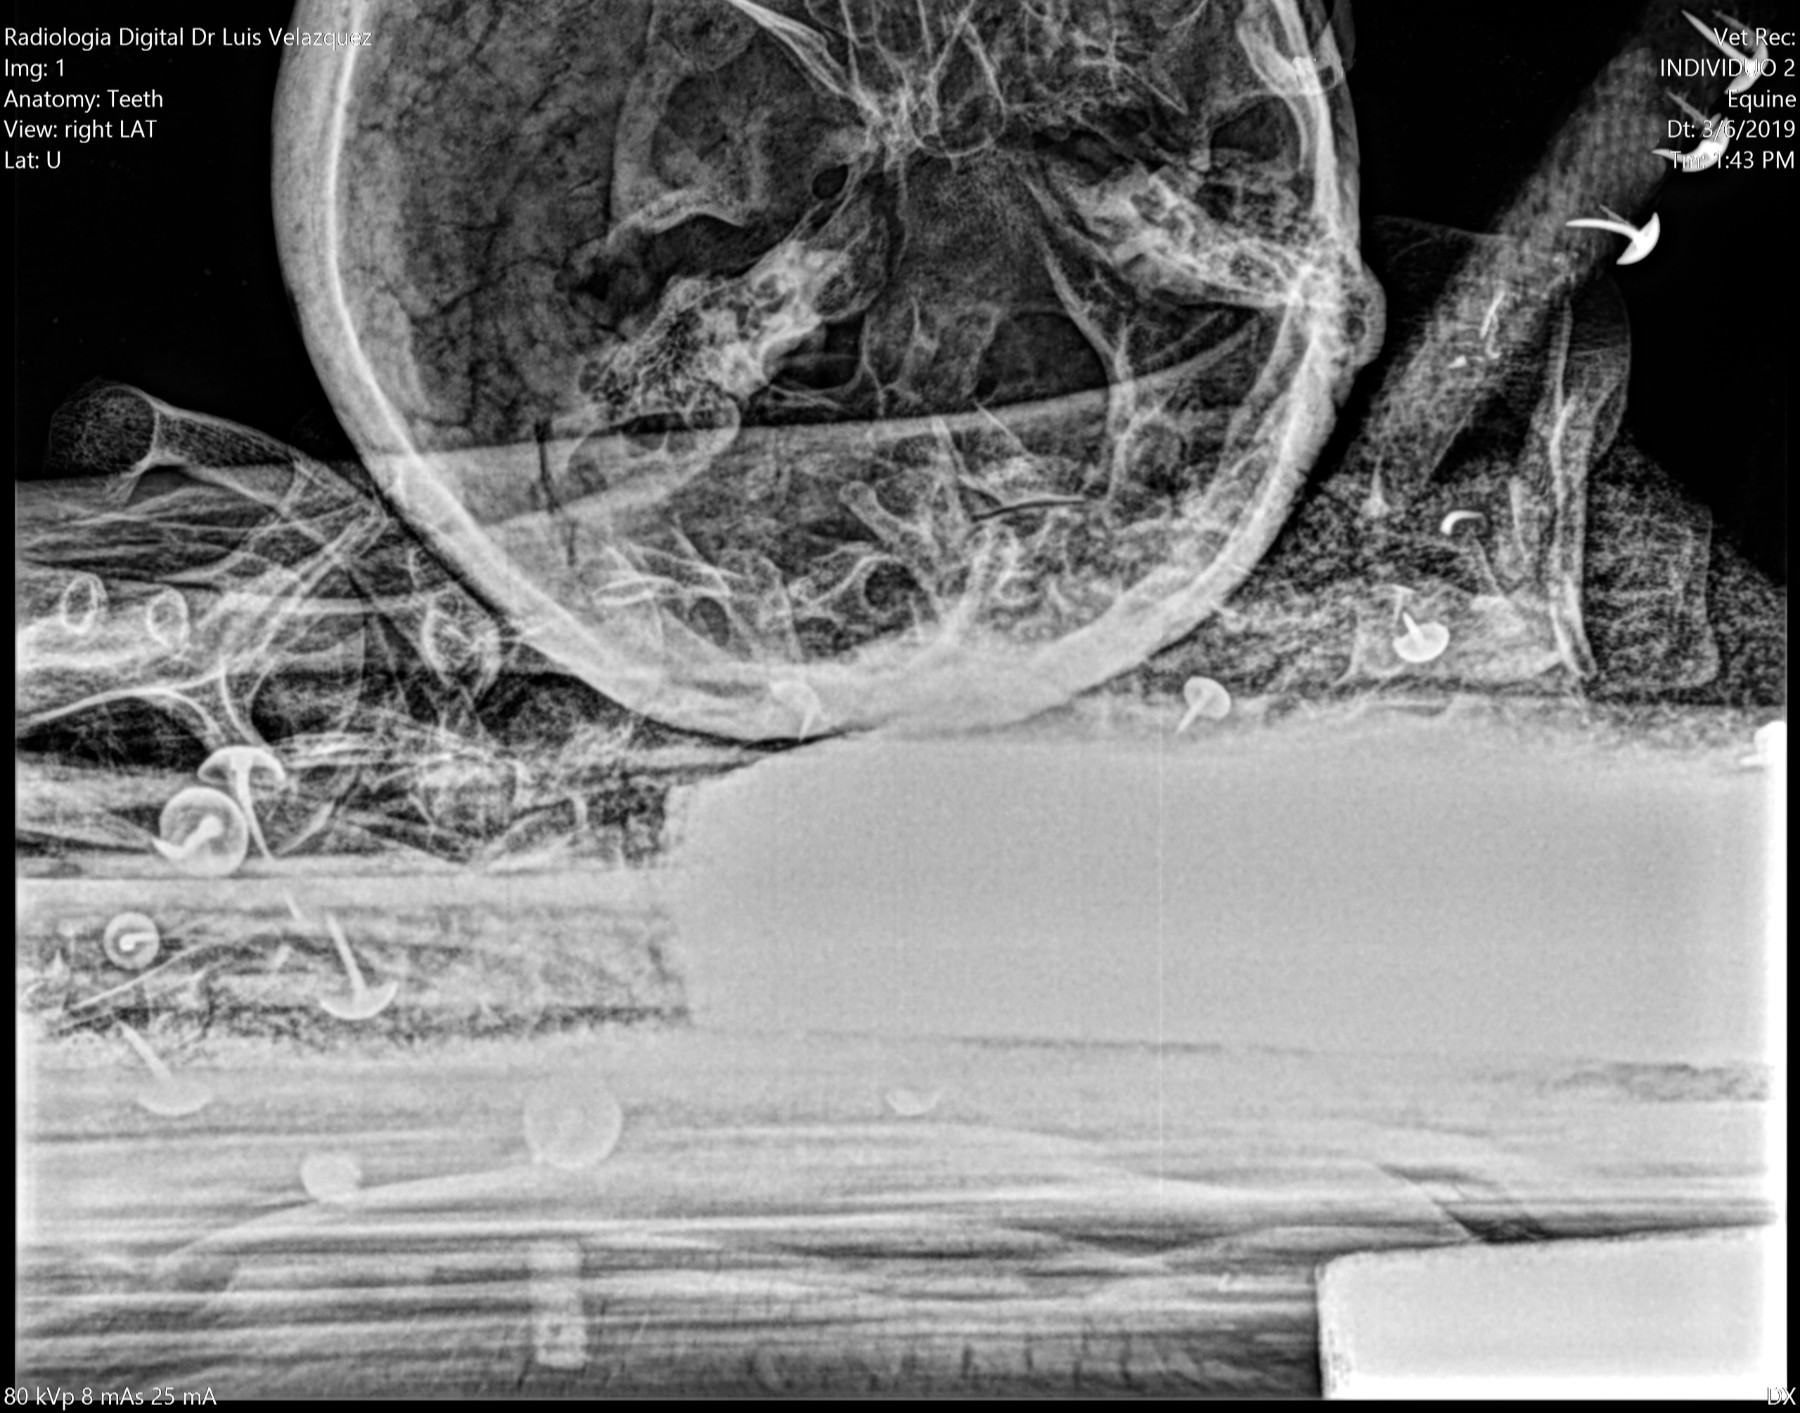

Radiología Digital como Herramienta Complementaria en el Dictamen de Bienes Muebles

Desde el descubrimiento de los rayos “X” y las placas radiográficas por Wilhelm Conrad Roentgen y su posterior difusión a través de la Asociación Físico médica de Wurzburg el 28 de diciembre de 1895, que fue la primera asociación que habló de los nuevos rayos que podían penetrar el cuerpo y fotografiar los huesos, ha habido muchos cambios tanto en la forma de obtener, procesar e incluso en la forma de visualizar, manejar y almacenar las placas radiográficas.